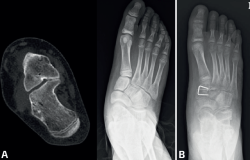

Proyección oblicua del pie a 45° (Figura 3A).

La CE se visualiza mejor en esta proyección, que presenta una sensibilidad del 90-100%. En condiciones normales, estos huesos no articulan entre sí, por lo que cualquier unión es altamente sugestiva de coalición. En las coaliciones óseas, se objetiva una unión completa con una prolongación del escafoides hacia el calcáneo, mientras que en las coaliciones fibrocartilaginosas se aprecia una disminución del espacio entre ambos huesos con bordes esclerosos e irregulares (pseudoarticulación).

La RM se está utilizando cada vez con mayor frecuencia, sobre todo en pacientes más jóvenes, en los que las coaliciones suelen ser fibrocartilaginosas. Esta técnica evita la exposición a radiaciones ionizantes, pero puede requerir anestesia general en niños pequeños debido al mayor tiempo necesario para su realización. Permite visualizar edema de la médula ósea, orientación anómala de la articulación y aplanamiento de la superficie articular. En coaliciones óseas se objetiva una imagen de la medular continua entre ambos huesos (Figura 3B)(7).

La TC ofrece imágenes en los planos sagital, coronal y transversal, así como reconstrucciones en 3D, siendo las proyecciones coronales las más informativas. Cualquier irregularidad en la carilla articular media entre el calcáneo y el astrágalo es sugestiva de coalición. Además, la TC permite medir el valgo del retropié, evaluando el ángulo formado entre la línea perpendicular del eje de la articulación del tobillo y la línea del eje del calcáneo. Un ángulo mayor de 16° se considera indicativo de un valgo aumentado (Figura 3C)(8).

Figura 3. A: radiografía oblicua del pie con coalición calcaneoescafoidea (CE); B: resonancia magnética mostrando una coalición CE; C: tomografía computarizada de una coalición calcaneoastragalina.